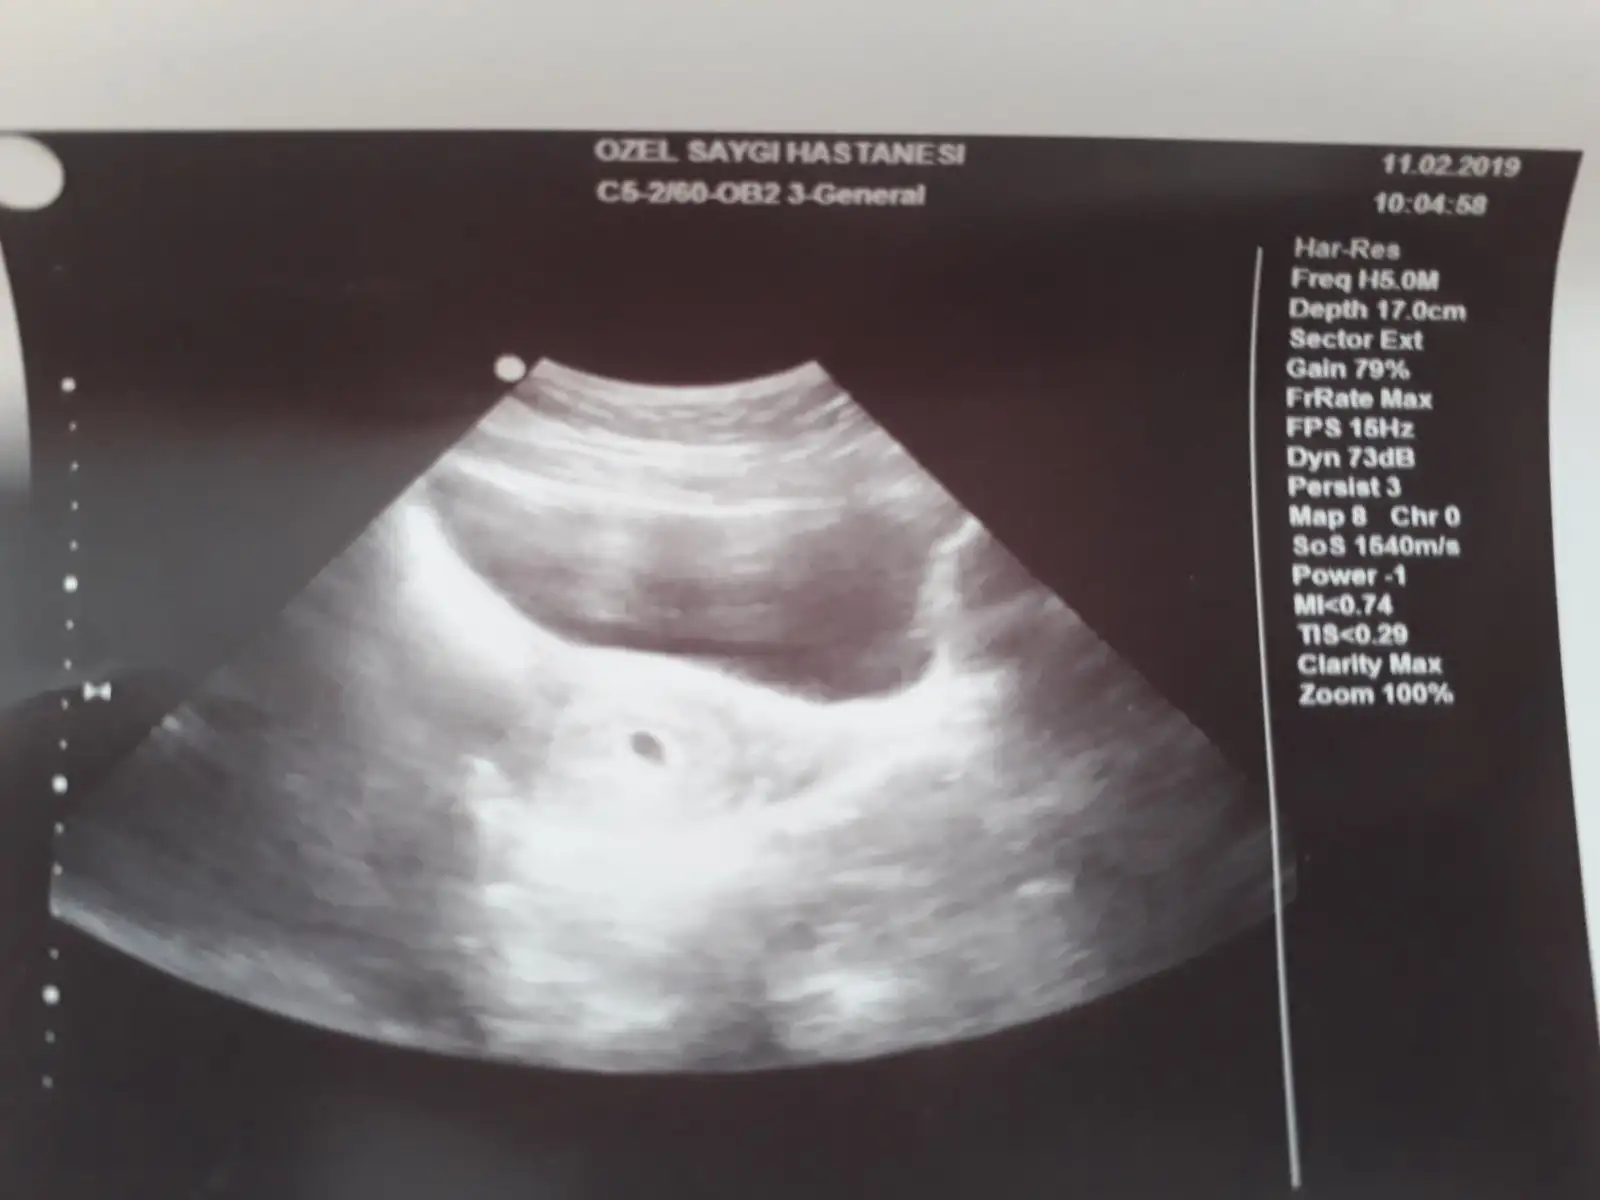

Merhsba canım 5-6 haftalık gayet normal güzel bi değer,belki 1hafta sonra bakar vitamin değerlerine rutin kontroleMerhabalar, doktor 2. Kontrolünde beta 10.000 civarı çıktı karından ultrasonla görebildi. 5-6 haftalık arasında dedi. Bir hafta sonra tekrar gel folik asit kullanmaya devam dedi ama başka bir şey demedi vitamin değerlerime falan bakması gerekmez m? Bu süreçte siz neler yaptınız? Çok merak ediyordum ve endişeleniyorum 1 hafta nasıl geçecek

canım benim çok fazla kasık ağrım vardı artık telaşa kapıldım ve acile gittik, orda dedim gebelik şüphemde var. Betahcgye baktılar. Sonra kadın doğumcuya gönderdiler. Keseye baktı hemen doktor.

Teşekkür ederim canım. Sağlıkla devam etsin inşallah hamileliğin. Rabbim keseyi görmeyide kalp atışını duymayıda kucağımıza almayıda nasip etsin hepimize.Hayırlı olsun canım artışın gayet güzel hep böyle devam etsin inşallah. Ben daha dün vajinal ultrason ile gördüm keseyi, hiçbir sorun yaşamadım, bi sakıncası da yokmuş zaten. Bence gönül rahatlığıyla baktırabilirsin